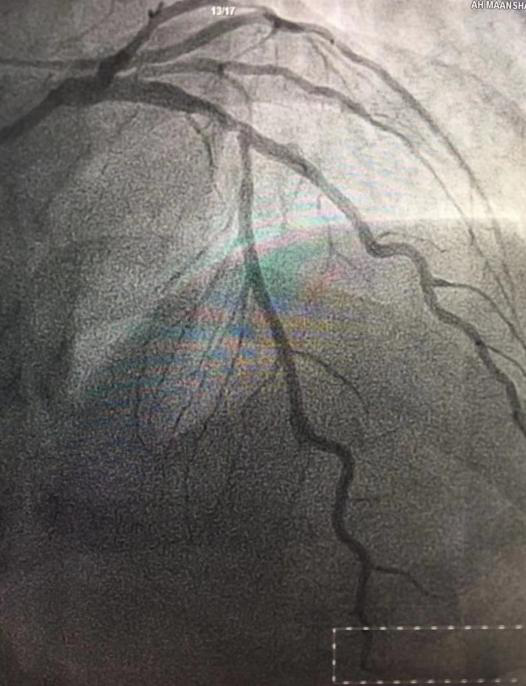

(術(shù)前) (術(shù)后)

時(shí)間就是生命!接診醫(yī)生為患者采集核酸后,胸痛救治團(tuán)隊(duì)立即啟動(dòng)應(yīng)急預(yù)案,在心血管內(nèi)科副主任董學(xué)濱的帶領(lǐng)下,手術(shù)團(tuán)隊(duì)配戴一級(jí)防護(hù)裝備,將患者繞行CCU直接接入導(dǎo)管室實(shí)施手術(shù)。手術(shù)團(tuán)隊(duì)首次經(jīng)歷穿戴防護(hù)服進(jìn)行介入操作,造影結(jié)果提示患者LAD近段80%狹窄、LCX細(xì)小、中遠(yuǎn)段狹窄95%,急診于罪犯血管LCX行球囊擴(kuò)張術(shù),手術(shù)結(jié)束后患者胸痛明顯緩解。介入手術(shù)期間,嚴(yán)密的口罩讓人呼吸困難,沉重的防護(hù)裝備給手術(shù)操作帶來(lái)了巨大的干擾,穿著鉛衣和防護(hù)服讓人汗流浹背,連簡(jiǎn)單的穿刺都變得艱難,但醫(yī)護(hù)團(tuán)隊(duì)齊心協(xié)力、沉著應(yīng)對(duì)、克服困難,最終憑借高超的介入技術(shù)順利化解了危機(jī),挽救了病人的生命!當(dāng)看到擴(kuò)張后的血管血流通暢,患者胸痛癥狀緩解,每個(gè)人的臉上都洋溢著燦爛、開(kāi)心的笑容。一周后,按照心肌梗死病例的救治原則,手術(shù)團(tuán)隊(duì)在患者高度病變的LAD處放入一枚支架。至此,心肌梗死患者的救治全部結(jié)束,目前患者痊愈出院。此次急性心?;颊叩某晒Λ@救,再次彰顯了醫(yī)院胸痛中心的救治能力。